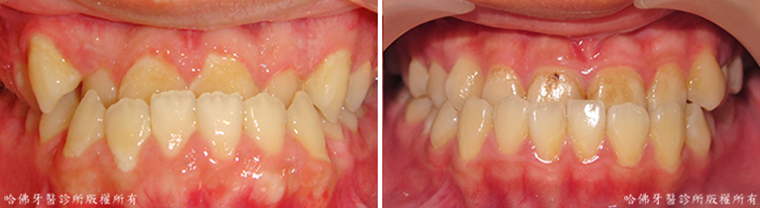

齒列不整,特別是存有牙齒擁擠的齒列不整,極易造成食物堆積的死角而引發蛀牙(圖2)。

(圖2)齒列不整,特別是存有牙齒擁擠的齒列不整,極易造成食物堆積的死角而引發蛀牙。藍色圈標定蛀牙位置。

當蛀牙尚在輕微的時候缺乏臨床症狀,蛀牙經常在嚴重時才出現酸痛腫脹等症狀。而當酸痛腫脹等症狀出現時,蛀牙已相當嚴重「而不」易治療(圖3)。

(圖3)當蛀牙尚在輕微的時候缺乏臨床症狀,蛀牙經常在嚴重時才出現酸痛腫脹等症狀。而當酸痛腫脹等症狀出現時,蛀牙已相當嚴重「而不」易治療。